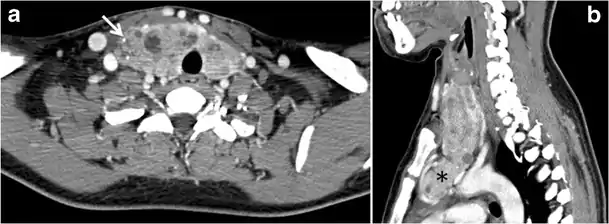

Malignancy can coexist within the goiter and a CT scan may give a clue if there are abnormal cervical lymph nodes and/or signs of invasion. Retrosternal extension (Fig. 15) could affect the surgical approach, as a lower extent may require a partial or total sternotomy to facilitate complete resection. Therefore, the distance of the retrosternal extent from the sternal notch should be measured on a sagittal image.[1]

Goiter

A goiter is an abnormal thyroid gland proliferation that manifests as multi-nodular, uni-nodular, or non-nodular diffuse glandular enlargement. A goiter is formed of solid matrix, colloid cysts, blood products, calcification, and fibrosis, and this heterogeneity may lead to variable appearances on a CT scan (Figs. 13, 1414 and and15)15). The US is more sensitive in evaluating thyroid nodules within a goiter; however, a symptomatic goiter may require surgical treatment with total thyroidectomy, and in this case CT plays an additional role in preoperative evaluation. Specific aspects for examination on a CT scan during the preoperative evaluation for goiter include extension, mass effect, and suspicious features of malignancy.[1]